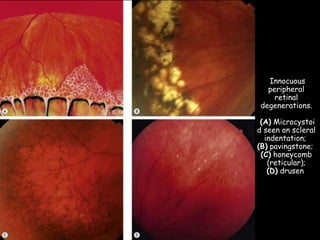

Innocuous

peripheral

retinal

degenerations.

(A) Microcystoi

d seen on scleral

indentation;

(B) pavingstone;

(C) honeycomb

(reticular);

(D) drusen